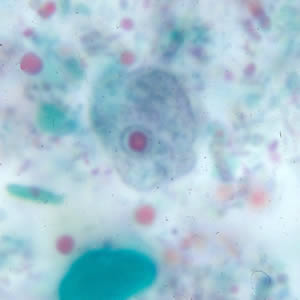

E.nana trophozoites

single nucleus with a blot-like karyosome